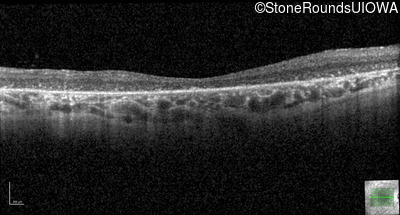

Optical Coherence Tomography - Right - 20/400 sc

Exemplar / OCT Stack